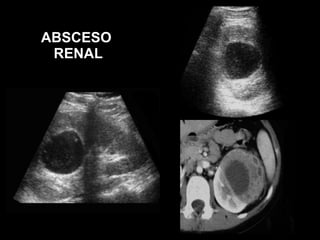

ABSCESOS RENALES

ABSCESO  RENAL